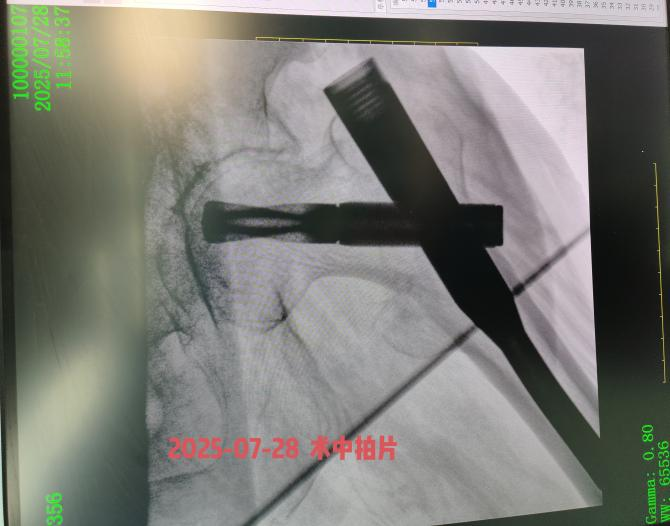

患者高龄,并发高血压、冠心病及肺部基础疾病,我院骨科团队迅速联合内科主任、麻醉科医师进行多学科会诊,评估病情,最终确定在腰麻下行右股骨粗隆间骨折闭合复位髓内钉内固定手术方案。安庆市第一人民医院骨科何流教授率领王亮主治医师通过 3 个小切口完成骨折复位与固定,手术顺利,术后恢复良好,术后5天李奶奶可以翻身自行坐起,目前在助行器辅助下部分负重行走。